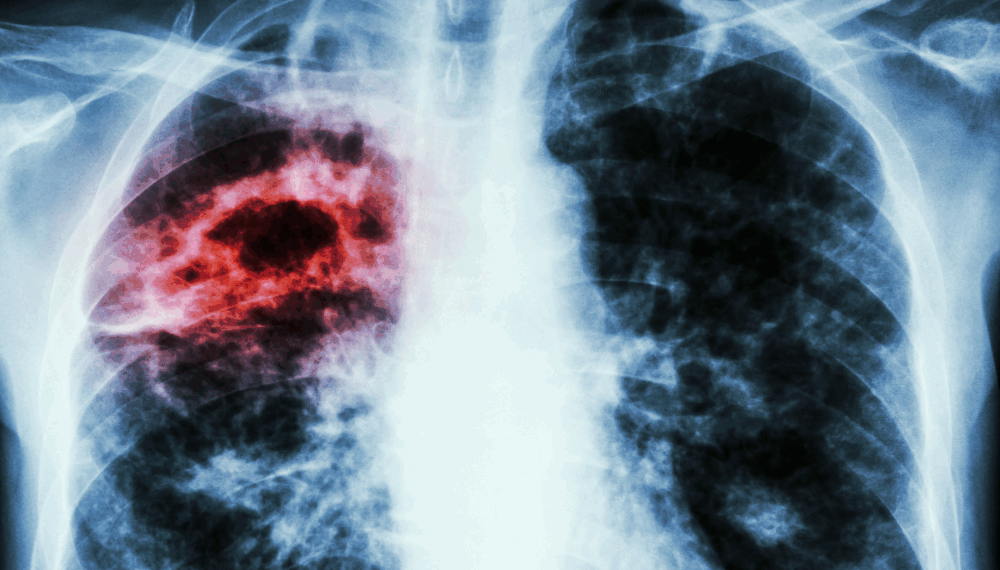

En cuanto al cáncer de pulmón -que se divide en dos tipos, el de células pequeñas (CPCP) y el de células no pequeñas (CPCNP)-, explicó que existen comportamientos y tratamientos diferentes para ambos.

El CPCP representa cerca del 15 % de los casos a nivel mundial, es más agresivo y suele presentarse en personas con historial prolongado de tabaquismo. En México, su tasa de supervivencia a cinco años es de apenas un 5 %.

Por otra parte, el CPCNP agrupa varios tipos de cáncer epitelial, como el carcinoma de células escamosas, de células grandes y el adenocarcinoma; además, está asociado al tabaquismo, aunque también puede afectar a personas que nunca fumaron.